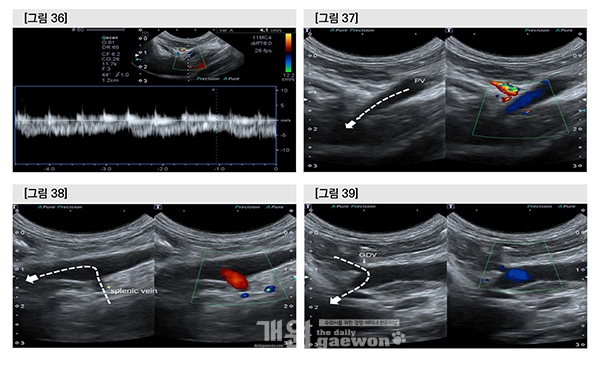

수술 1일차에 bulging된 vessel 안에서 fluttering material이 관찰되었고, thrombus가 의심되었다.

D-dimer는 0.7mg/L(0-0.3)으로 다소 상승하여 있었으나 수술 직후이므로 직접적인 관련성은 확실하지 않았다. Portal vein flow velocity는 거의 측정되지 않았으므로 portal vein 내에서 혈액의 정체와 간의 bypass가 동시에 일어나고 있음을 유추할 수 있었다.

PV 내에서 thrombus 형성이 의심 되었으므로 dalteparin 150 IU/kg tid로 증량하였다.